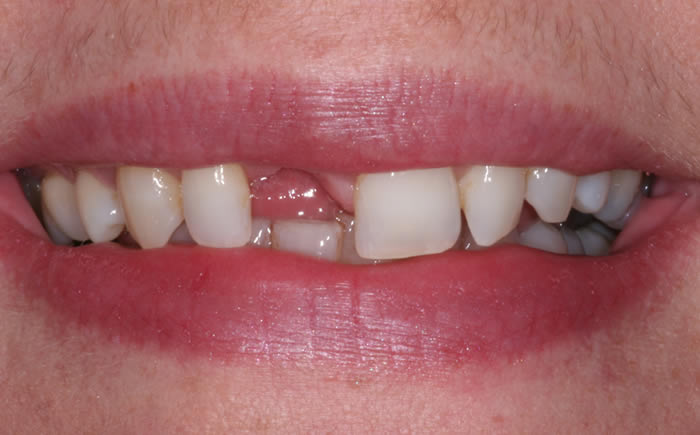

Before & After Gallery

More front teeth replaced by dental implants

Case Three (4 images)